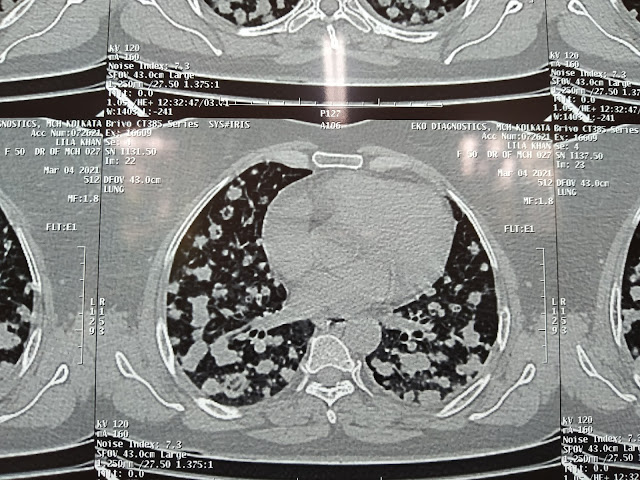

" Flower in the lung sign " 🌺

This 50 years young female presented with occasional dry cough and chest pain during coughing in our OPD ,on x ray looks like canon Ball Metastasis and that was confirmed by CT Thorax. The CT plate looks beautiful overall like flowers inside lung parenchyma, on biopsy came to be 'non small cell carcinoma' .